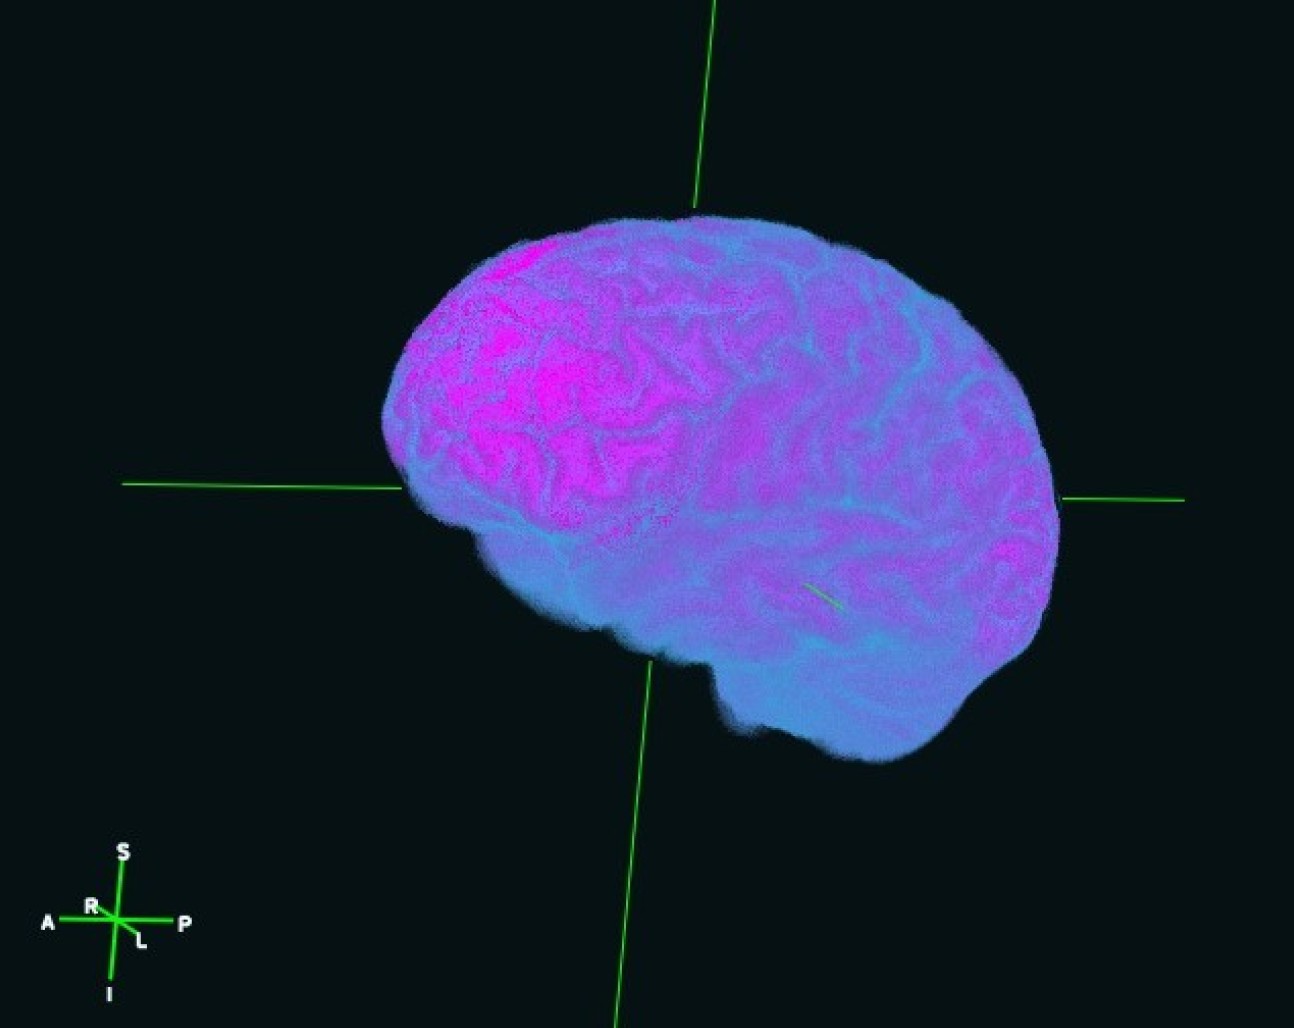

Golden Brain - Brian Schilder (PhD Student: Skene lab)

"3D surface reconstruction of the brain of the artist from 2D structural MRI scans, rendered with three.js."